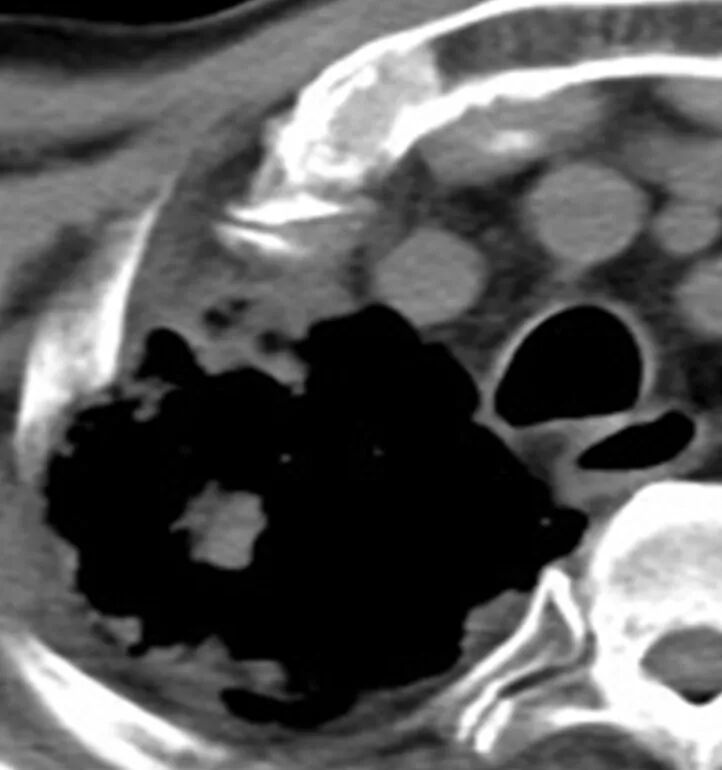

经过王剑飞和肿瘤中心MDT团队的认真讨论,确诊王大伯为右肺恶性肿瘤。“那要手术么?”家属着急地询问着。“大伯80多岁了,心肺功能也不好,手术治疗不耐受的,还是考虑局部治疗,也就是放射治疗”,王剑飞耐心解释着。 经过考虑,大伯和家属都接受了放射治疗的建议。放疗中心副主任刘文君、主治医师阮龙飞为王大伯详细制定了右肺上叶肿块根治性放疗的治疗方案。很快,王大伯便正式开始了治疗。 一年过去了,王大伯早已结束了治疗,而他的定期复查结果令人欣喜——右肺上叶肿块持续缩小,现在已经几乎消失了! “还好听医生话还算及时!”每次看到复查报告,王大伯都十分高兴,一再感谢肿瘤科团队的帮助与悉心照料。 王剑飞提醒市民:发现肿瘤并不是最可怕的,可怕的是不重视或不配合治疗,这是医生最无能为力的局面。 治疗前 治疗结束 治疗结束后2月 治疗结束后10月